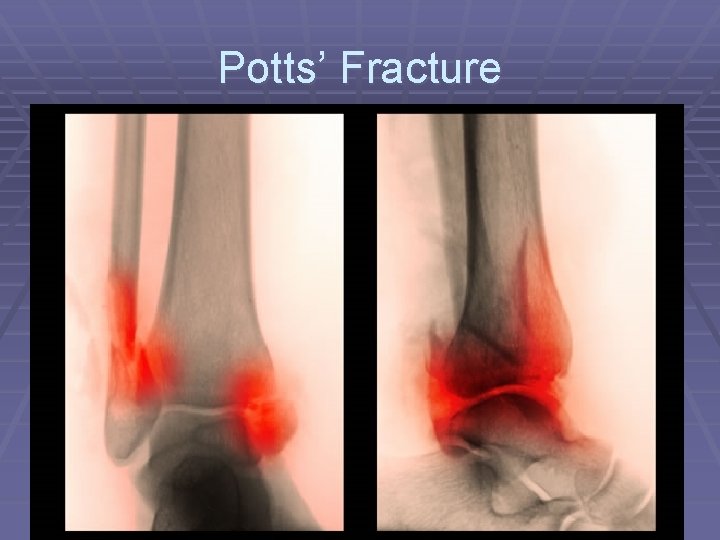

Potts’ Fracture